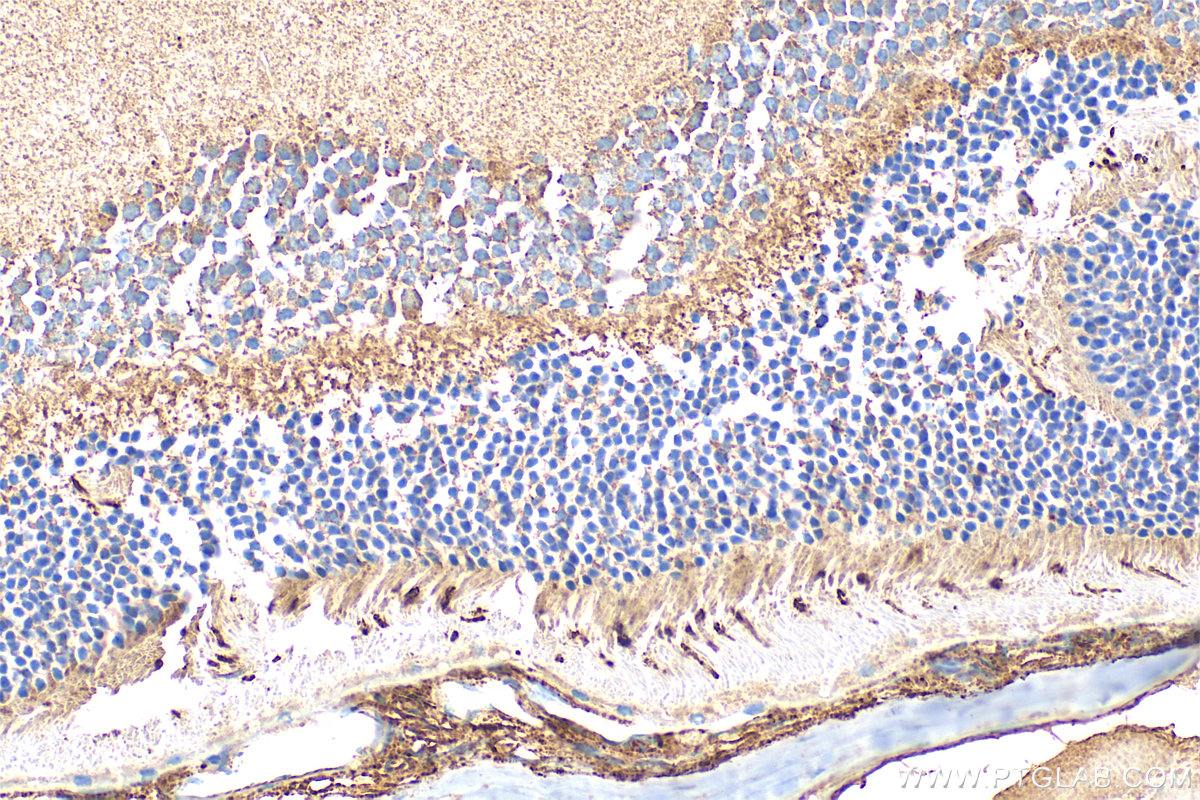

| Positive IHC detected in | mouse eye tissue Note: suggested antigen retrieval with TE buffer pH 9.0; (*) Alternatively, antigen retrieval may be performed with citrate buffer pH 6.0 |

24660-1-AP targets OPN1SW in IHC, IF-P, ELISA applications and shows reactivity with human, mouse, rat samples.